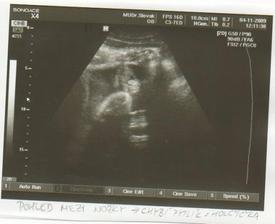

13. Květen: Dneska jsem byli na vyštření. Dostali jsme obrázek, průkazku a kufřík se spoustou nezbytných maličkostí. Z bříška nám Rupík zamával ručičkou a pak si chvilku hrál na schovku, nakonec se ale krásně ukázal a nechal se i vyfotit. Všechno je v nejlepšímpořádku, máme negativní toxoplazmozu, HIV a žloutenky, krevní skupinu 0Rh+. Taky jsme dostali žádanku na "velký" ultrazvuk do Brna, kde si zjistíme pravděpodobnost Downova syndromu a zároveň necháme vyšetřit i genetiku, kvůli tomu oparu. Na vyšetření jdeme 3.6. a půjde s námi i Mišáček. Ráno jsme se oba "rozplývali" nad fotkou (já víc, samozřejmě 🙂 ), a taky jsme si pro jistotu vyrobili hned několik kopií. Už se moc těšíme, až budeme vědět, že je v bříšku všechno v pořádku.